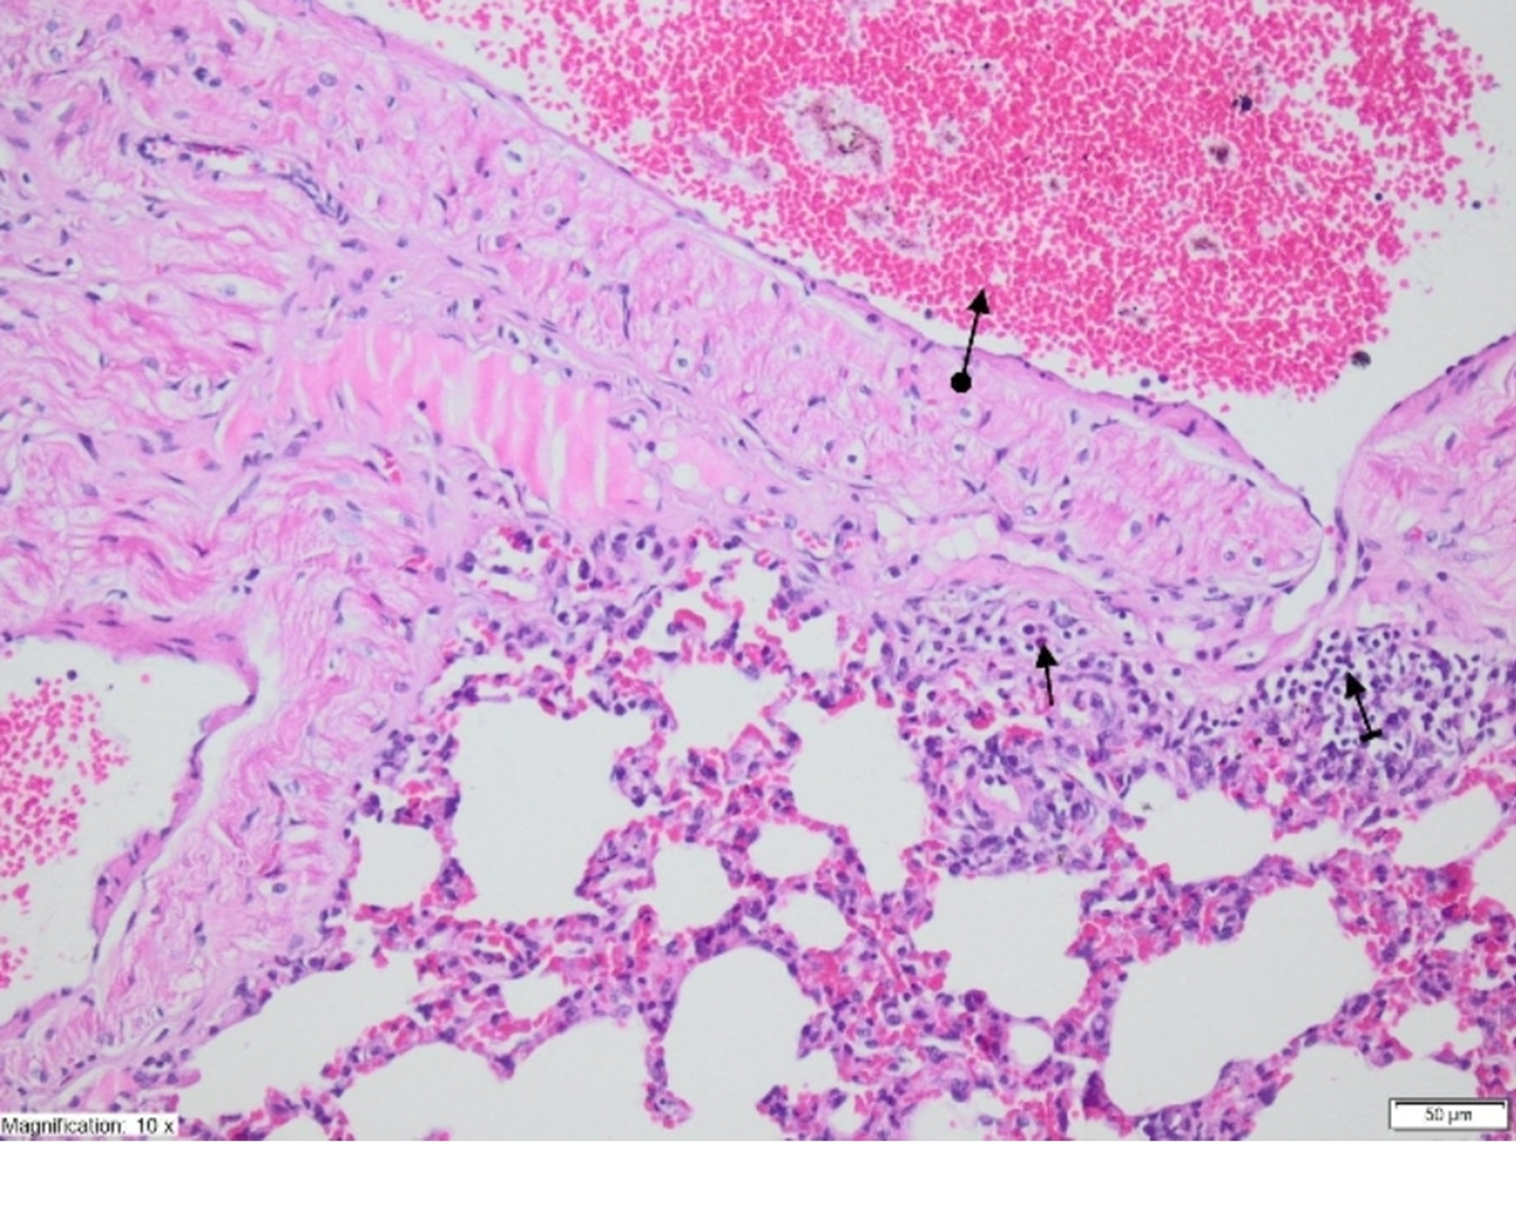

On histopathological examination, the alveolar vein, bronchiole structures and pleural mesothelium were identified as normal in pulmonary tissues in the SG group (Figure 4). However, significant areas of alveolar degeneration, edema and hemorrhage were observed in the pulmonary tissues of the LIR group (Figure 5). Congestion, PMNL and lymphocytic infiltration were observed in the lung tissues in the LIR group (Figure 6). In the lung tissue of the RLIR group, the pleural mesothelium, and alveolar, vascular and bronchial structures were identified as normal, which was similar to the observations in the SG group (Figure 7).